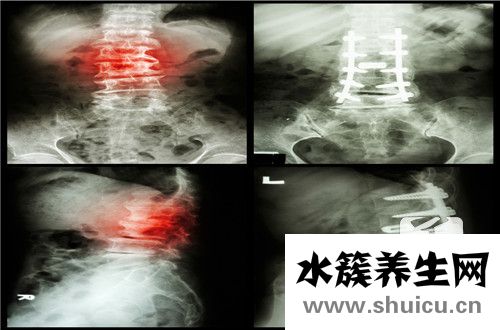

4、頸椎病也可能造成這類病癥

很多人的頭昏狀況有可能是頸椎病造成的,長期性的低下頭,不常常開展一些適度的拉伸運動,也有一些別的原因會造成頸椎病的產生,這類狀況會被壓迫的血管,進而出現短暫性的腦供血不足的狀況,因此 頸椎病也是應當考慮到在里面的;溫馨提醒:每日適度的頸部左室健身運動,再加頸部操,能夠 推動血液的循環系統,緩解病癥的產生。

脊柱是我們頸部橫穿背部的一段,可以說是背部的脊柱。我們可以根據脊柱左右徑的大小來區分是否狹窄。一般的判斷依據是小于13mm就比較窄,小于10mm就肯定窄。進行手術醫療時,我們需要固定螺釘。所以如...